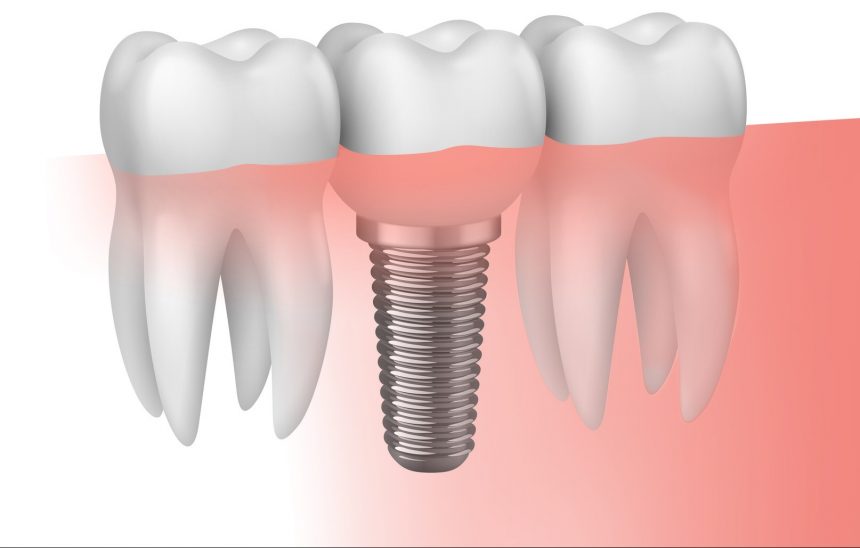

Implantes

Los implantes dentales se utilizan para reponer los dientes perdidos o ausentes en boca. Los implantes son unos pequeños tornillos...